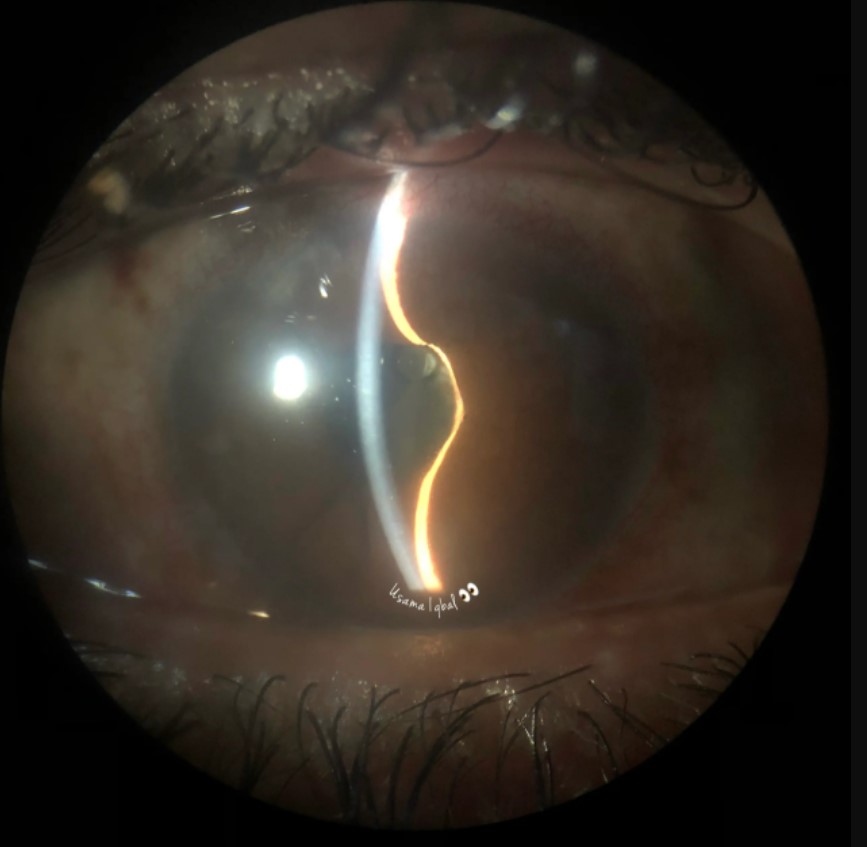

이때 염증물질들이 동공과 수정체 사이의 틈사이에 달라붙게되면,

동공차단(pupillary block)이 발생할수 있습니다.

차단된 동공 이외에 전방과 후방사이의 연결 통로가 없게되면,

후방에서 전방으로 방수가 흘러나오지 못하고 후방에 점점 물이 고이게됩니다.

이는 홍채볼록(iris bombe)로이어지고, 이는 결국 전방각의 물리적 폐쇄(angle closure)로 이어집니다.

술후 염증으로 인한 동공 차단 -> 홍채 볼록 -> 전방각의 물리적 폐쇄 -> 안압 상승 & 전방의 좁아짐